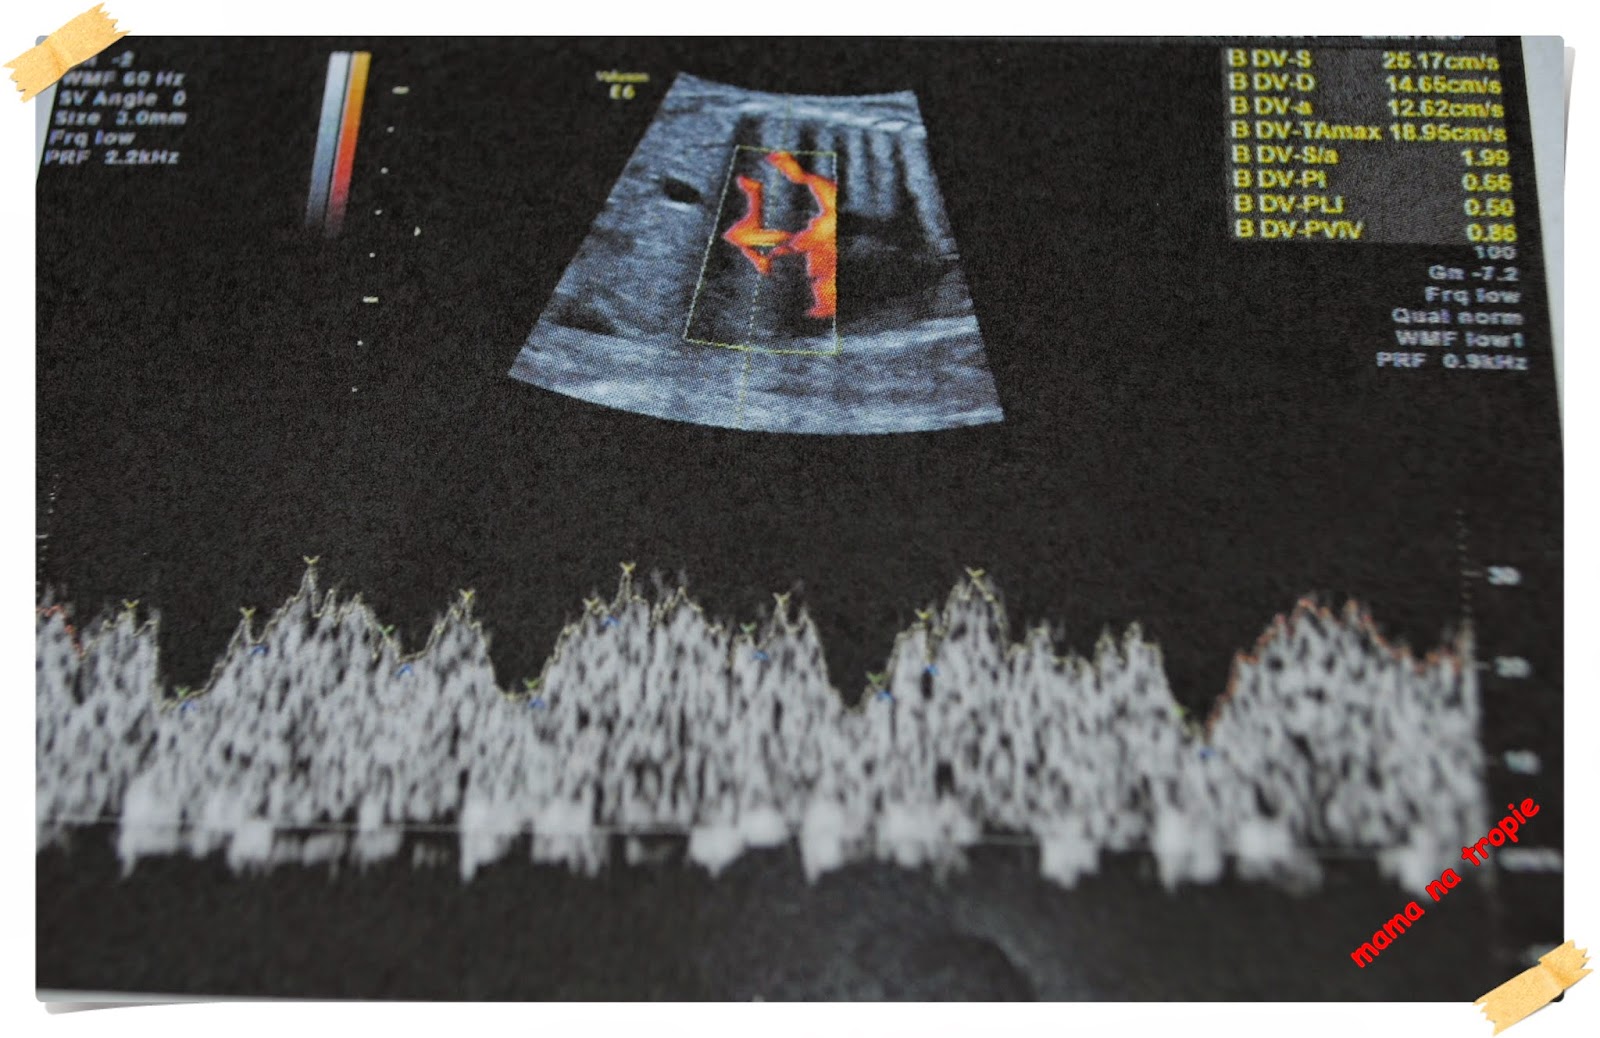

24-26 tydzień. Czas leci… maluchy rosną tak jakby były pojedyncze a nie we dwójkę, więc i matka ma coraz większe, odczuwalne fizycznie problemy. Na usg niestety coraz mniej widać, gniota się tam maluszki, chowają przytulając do siebie nawzajem oraz do ścian macicy czy też wskakując mi pod żebra. Tym razem chciałam Wam pokazać przepływy w pępowinie oraz w sercu jednego z bliźniaków – są jak najbardziej prawidłowe. A TTS-u ani widu ani słychu, choć lekarz ostrożnie zaznacza, że zdarzył mu się nawet taki który się zaczął w 30 tygodniu. Wyniki troszkę spadły jeśli chodzi o żelazo, więc dostałam do spożycia Sorbifer. Nie najgorszy w smaku i nie najtrudniejszy do spożycia, patrząc na to, że nie umiem totalnie łykać tabletek. Nie podrażnia mi tez żołądka więc jest nie najgorzej.

przepływy na pępowinie bliźniaków